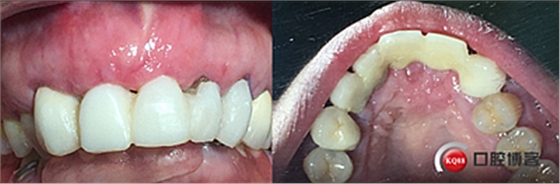

患者女性,52歲,缺失三顆牙,骨性前突,頜弓窄,身高175,魁梧,放了三顆牙是不是有點細?左上3開膠了,牙體有腐蝕。

鄰牙重新備牙,制作臨時樹脂橋體,缺牙區(qū)三顆變?yōu)閮深w。下圖是術后一個月口內(nèi)照。

大家看看前后對比,效果不錯。